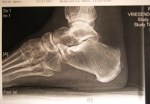

A little after noon we presented ourselves at Faulkner hospital for a fourth second opinion. First stop was a new X-ray – required for any new patient (the darn machines have to be paid for, no?), even though I was carrying a huge envelope with all sorts of pictures that were taken in July). Doc #4 referred to the operation as a heroic one which gave us pause. After seeing me walk with ease on tippy toes (‘you shouldn’t be able to do that’) he essentially counseled against a surgical intervention and proposed as an interim measure orthotics and a return visit with a scan to establish a baseline and follow me closely through twice yearly visits.